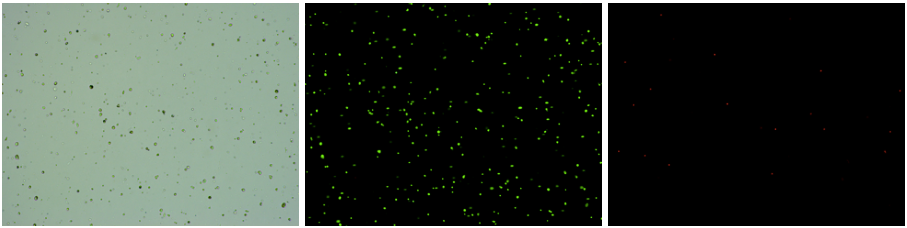

人腎癌樣本,細胞活率:94.69%,結(jié)團率:6.6%